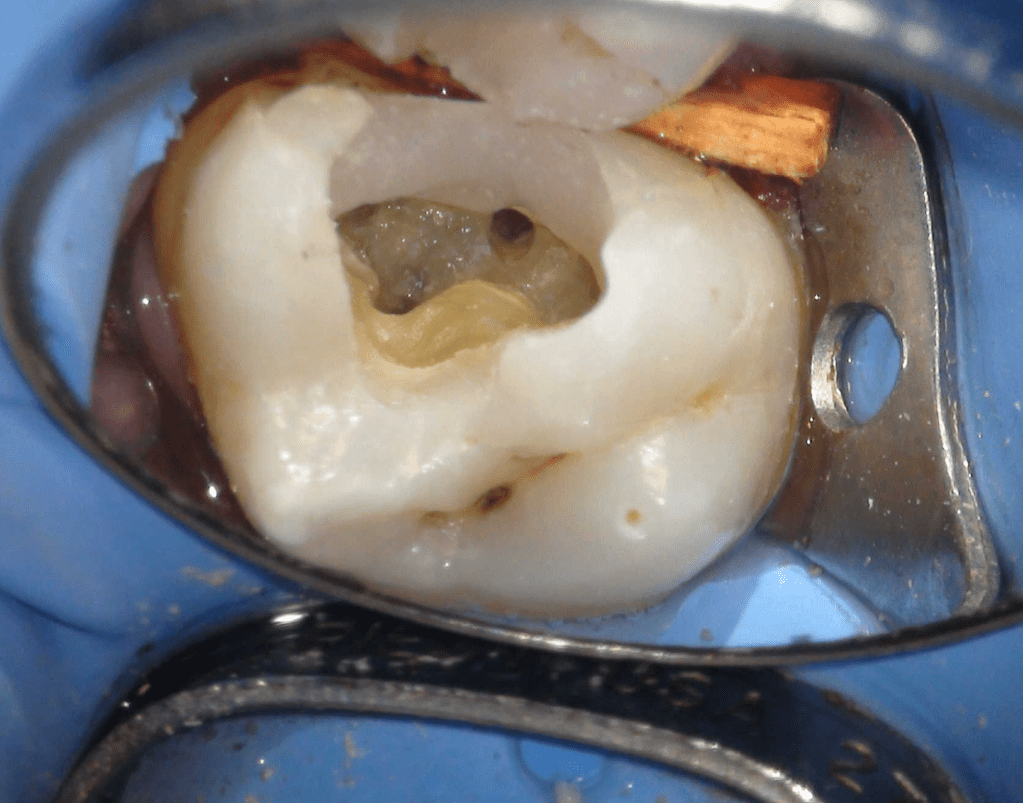

Pulpotomía biodentine + reco preendio